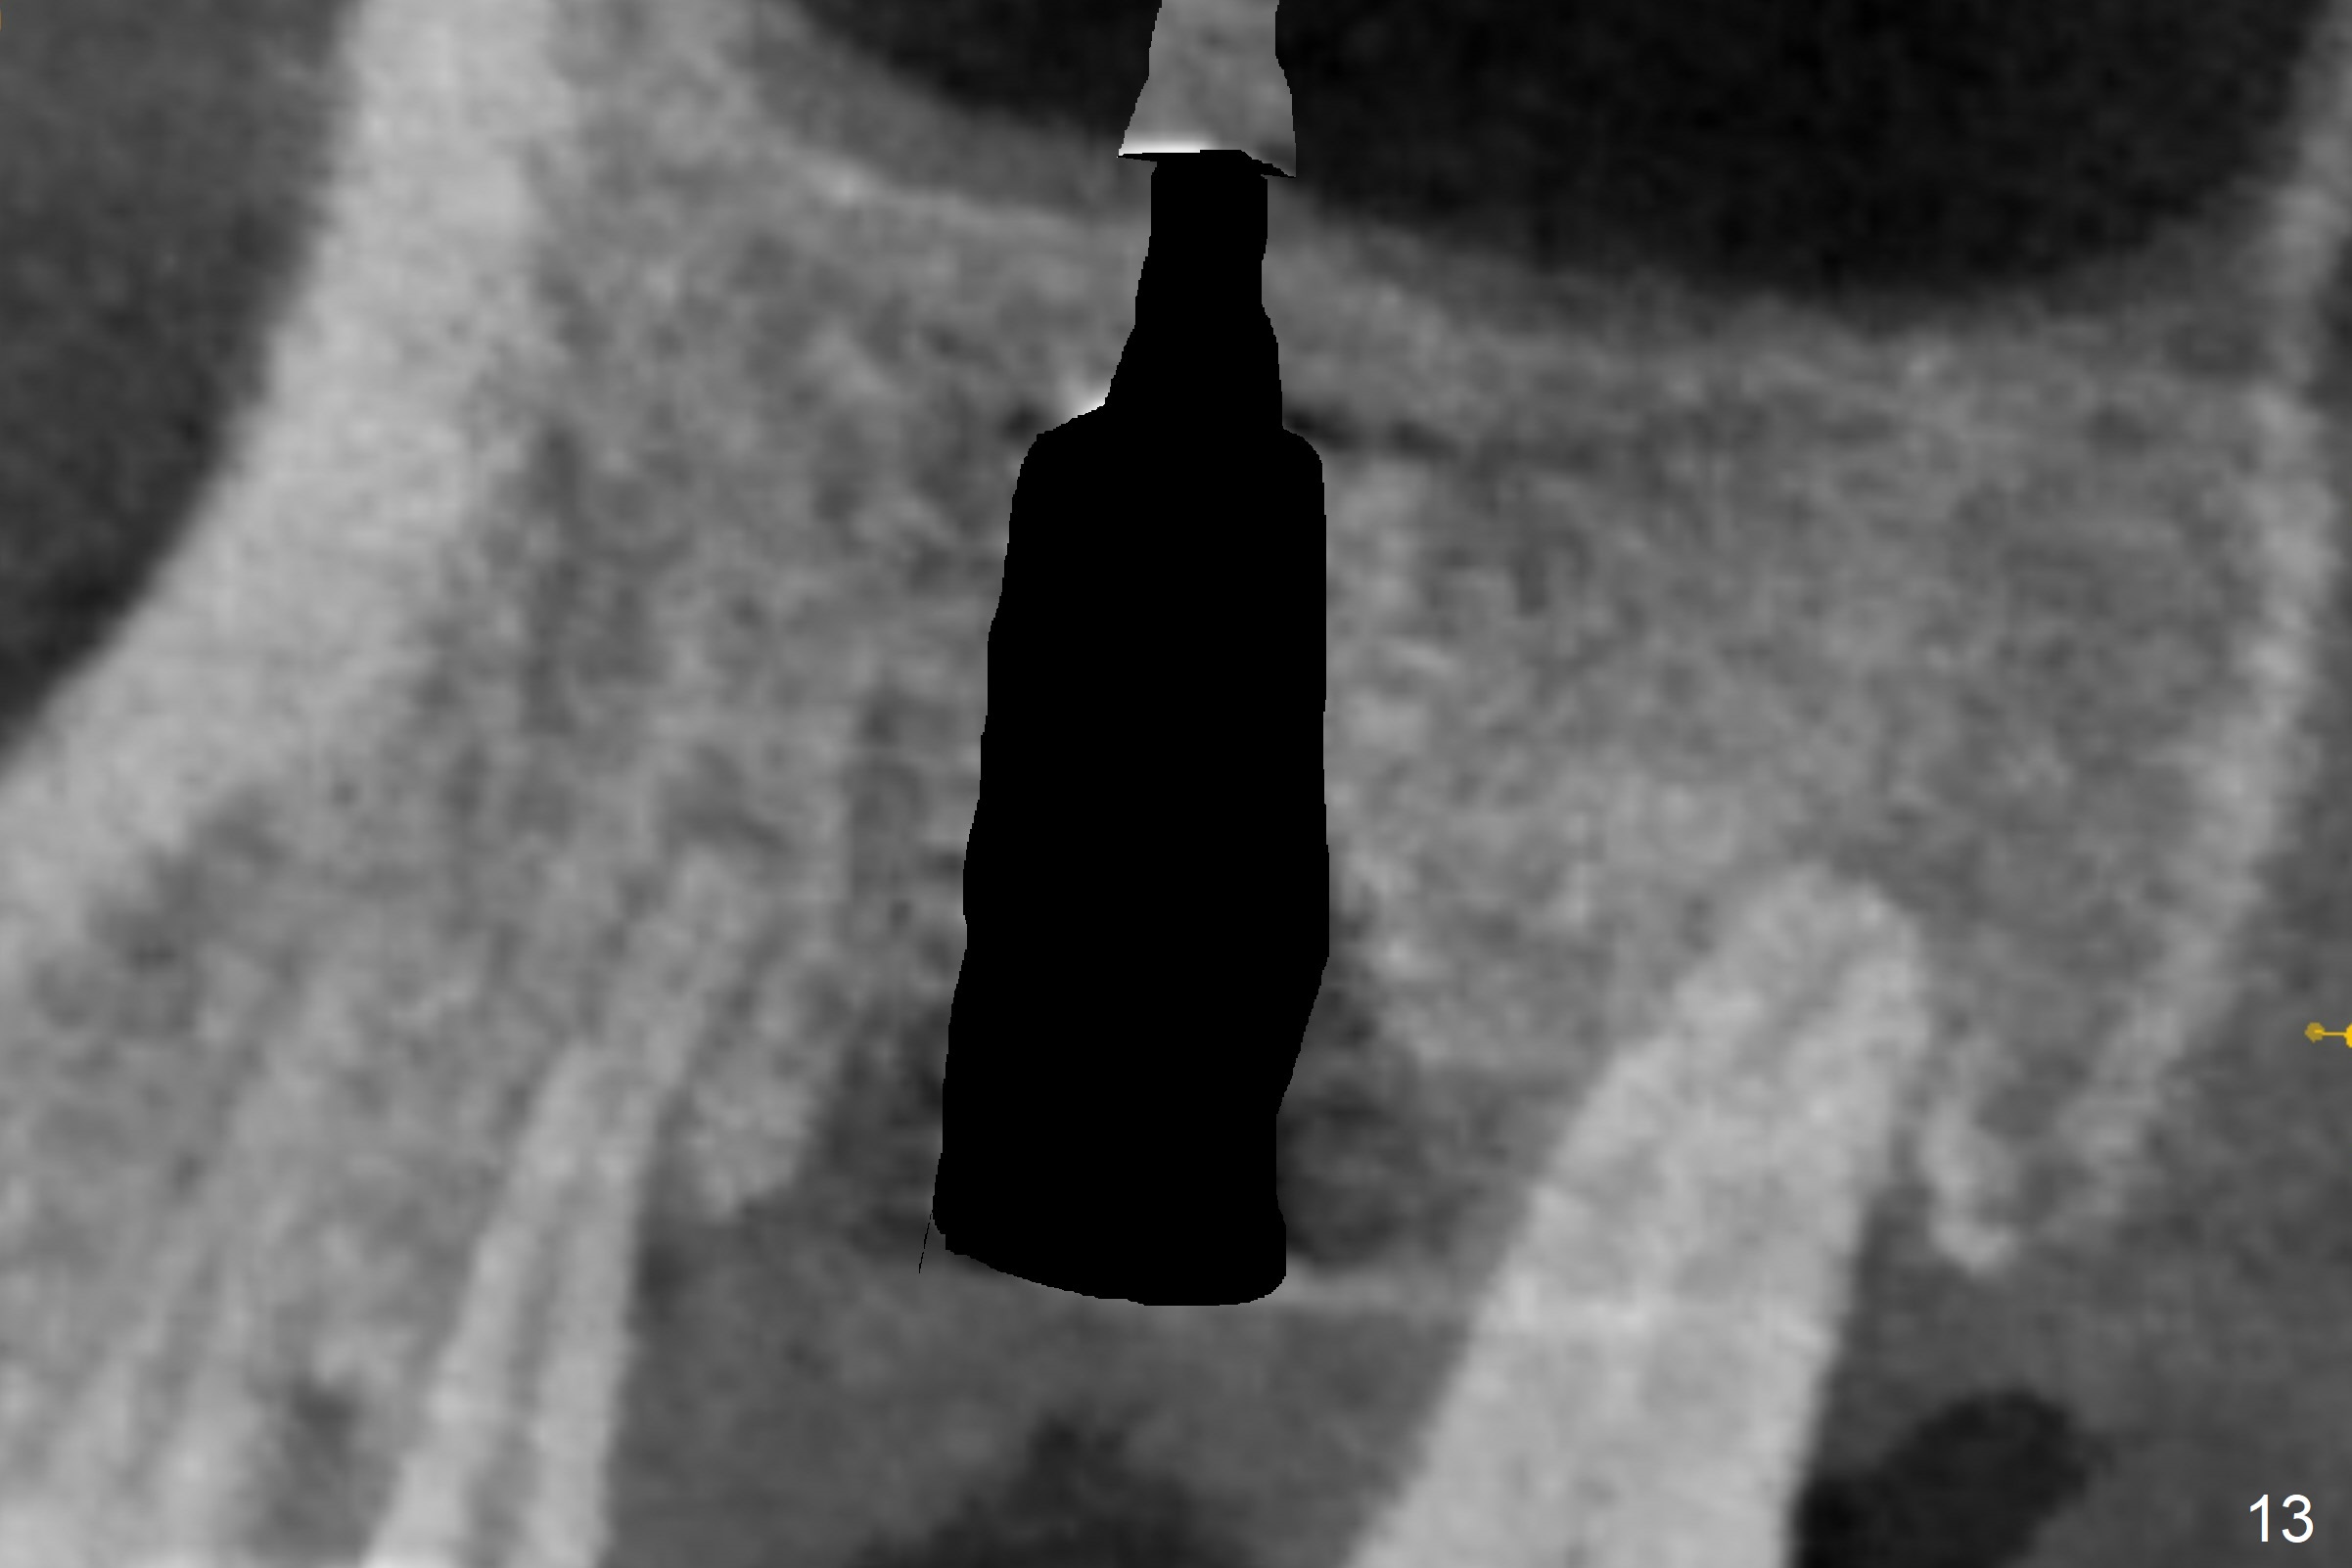

The amount of the bone graft mesial and distal the implant seems to reduce 3 and 4 months postop, respectively (Fig.6,7 arrowheads). When the acrylic is cut off 4 months postop, the bone graft is loose. The gingiva is unhealthy. The abutment and implant are loose. A healing abutment is placed (5x4 mm). The implant is torqued to 35 Ncm 6 months postop with the healing abutment reapplied. The patient will return for follow up nearly 9 months postop. A larger healing abutment will be used if the implant is stable. Two weeks later, use a smaller restorative abutment for easy impression. In fact the implant is unstable with #15 mesial shift due to abnormal occlusion with #17 (Fig.8). Bone density around the implant is low (* in Fig.9 (PA), 10,11 (CT sagittal, coronal sections)). A healing screw is placed for self healing. A 2nd option is to remove the implant (Fig.12), BEB (Fig.13) and place the implant deeper (Fig.14) or larger one (5.5-6.5x13 mm). The 3rd option is to place larger and longer implants (Fig.15 (tapered), 16 (cylindrical)). The implant access has partially closed 14 months postop, but there is a small buccal opening with sanguine exudate. Incision reveals severe bone loss around the implant; the mobile tooth #15 is extracted (Fig.17). After debridement and irrigation with normal saline, Vera Graft (Fig.18 *) and Collagen plug are placed with periodontal dressing.

Purulent discharge persists postop. Remove the implant and replace with IS one.